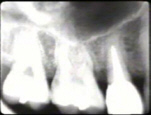

El examen de la condición periodontal se lleva a cabo en la dentición completa, el profesional registra las profundidades del surco gingival (bolsas periodontales) y el sangrado de las mismas. Si juzga necesario tomará radiografías periapicales, complementar el diagnóstico periodontal.

Se realizaron radiografías periapicales de todos los dientes, estas demostraron la perdida de nivel óseo en aproximadamente un 1/3 a 1/2 de la longitud de la raíz. En algunas situaciones, como en el  premolar  superior, la perdida de tejido óseo  en los espacios interproximales era muy significante.